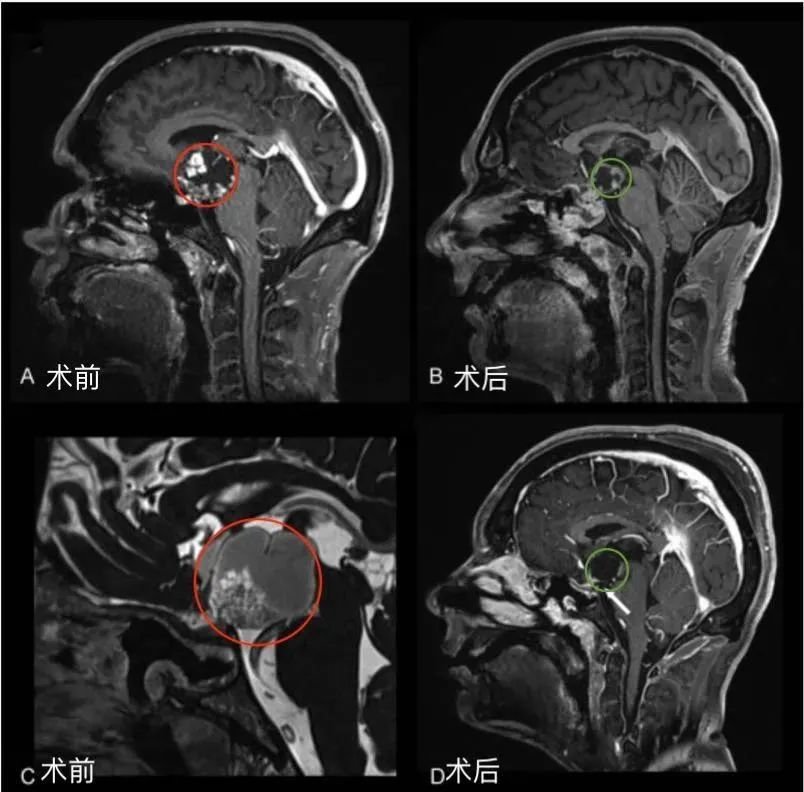

35岁男性后视交叉性较大颅咽管瘤